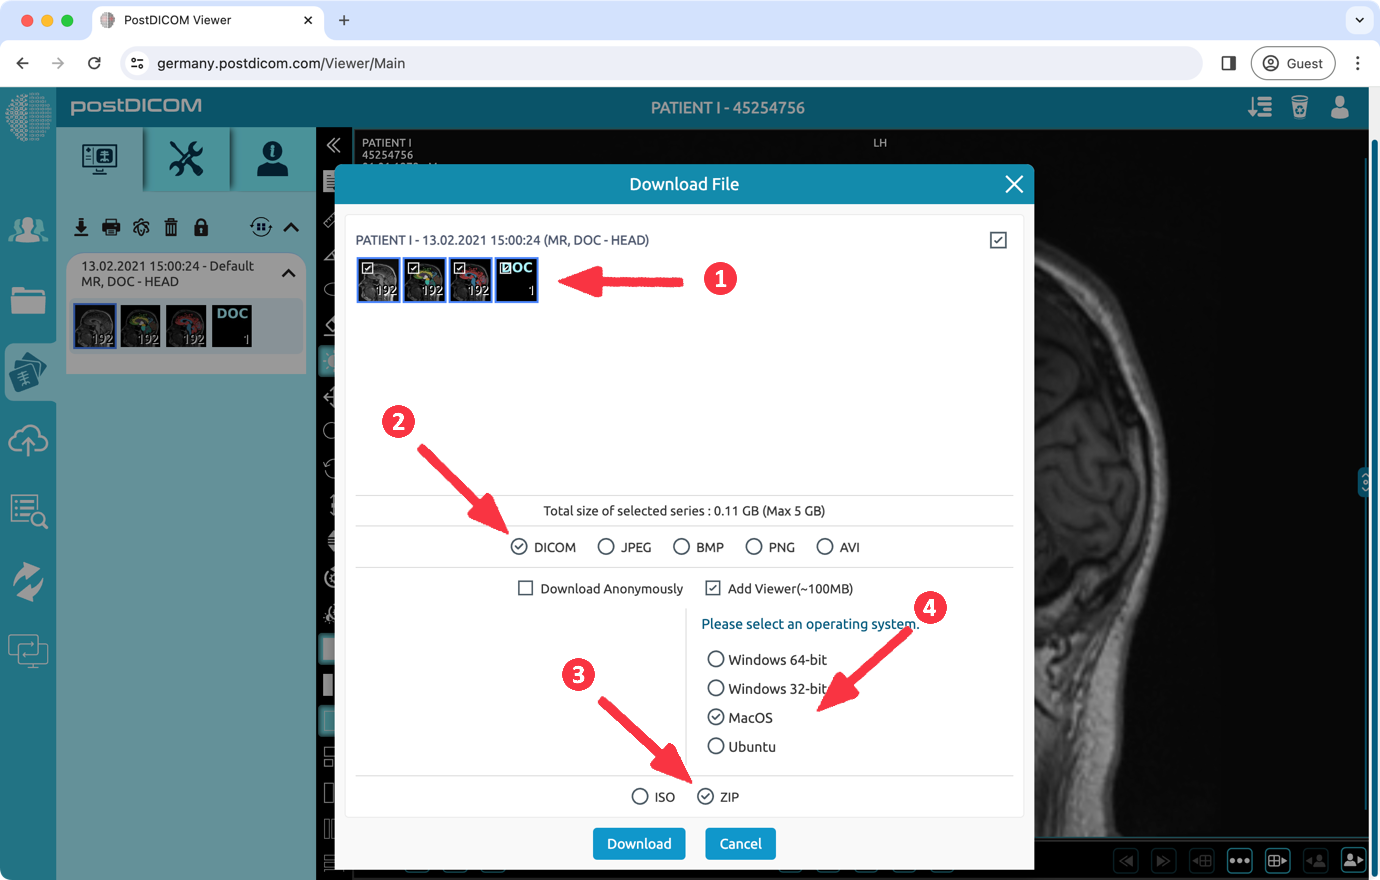

(1) Select the series to be downloaded. (2) Select 'DICOM' format. (3) Select 'ZIP' format you want to download. (4) To add a viewer, you should select the 'Add Viewer' option and select the MacOS operating system. This option adds the 'PostDICOMCDViewer' application, which is approximately 100 MB in size. Finally click the 'Download' button.